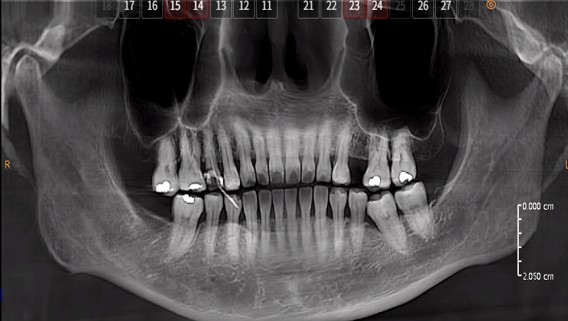

Panoramic radiograph shows inadequate obturation (radiolucent area) with white radiopaque material in the root canal of tooth 15